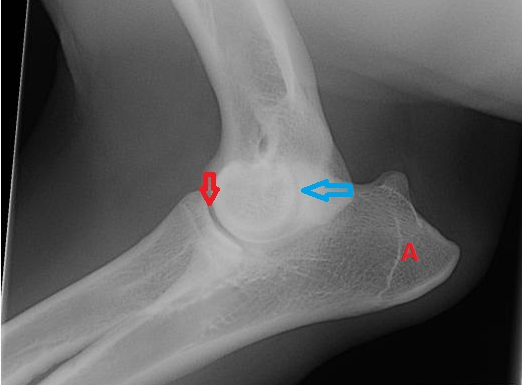

red and blue arrow

what is the third joint that makes up the elbow?

red- humeroradial joint

blue arrow- humeroulnar joint

third joint- radioulnar joint

medial coronoid process